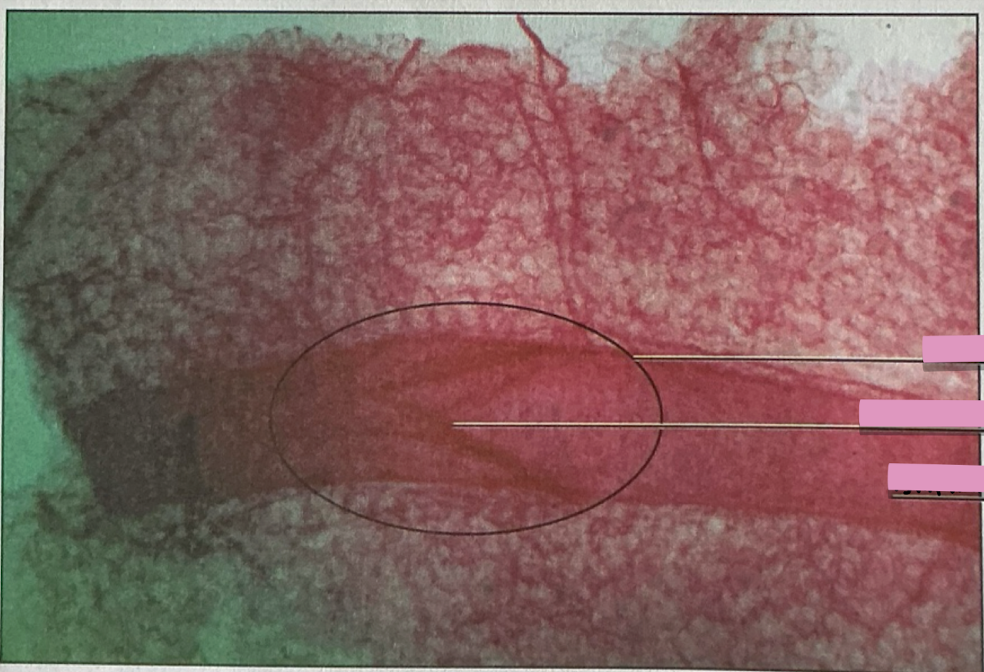

lympatic vessel valve